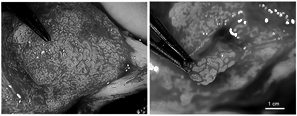

▲手术取精中

手术开始仅15分钟,许蓬院长便凭借精湛娴熟的技术成功获取了样本。样本被火速送至实验室后,李宏图副院长在短短五分钟内就锁定了活动精子。